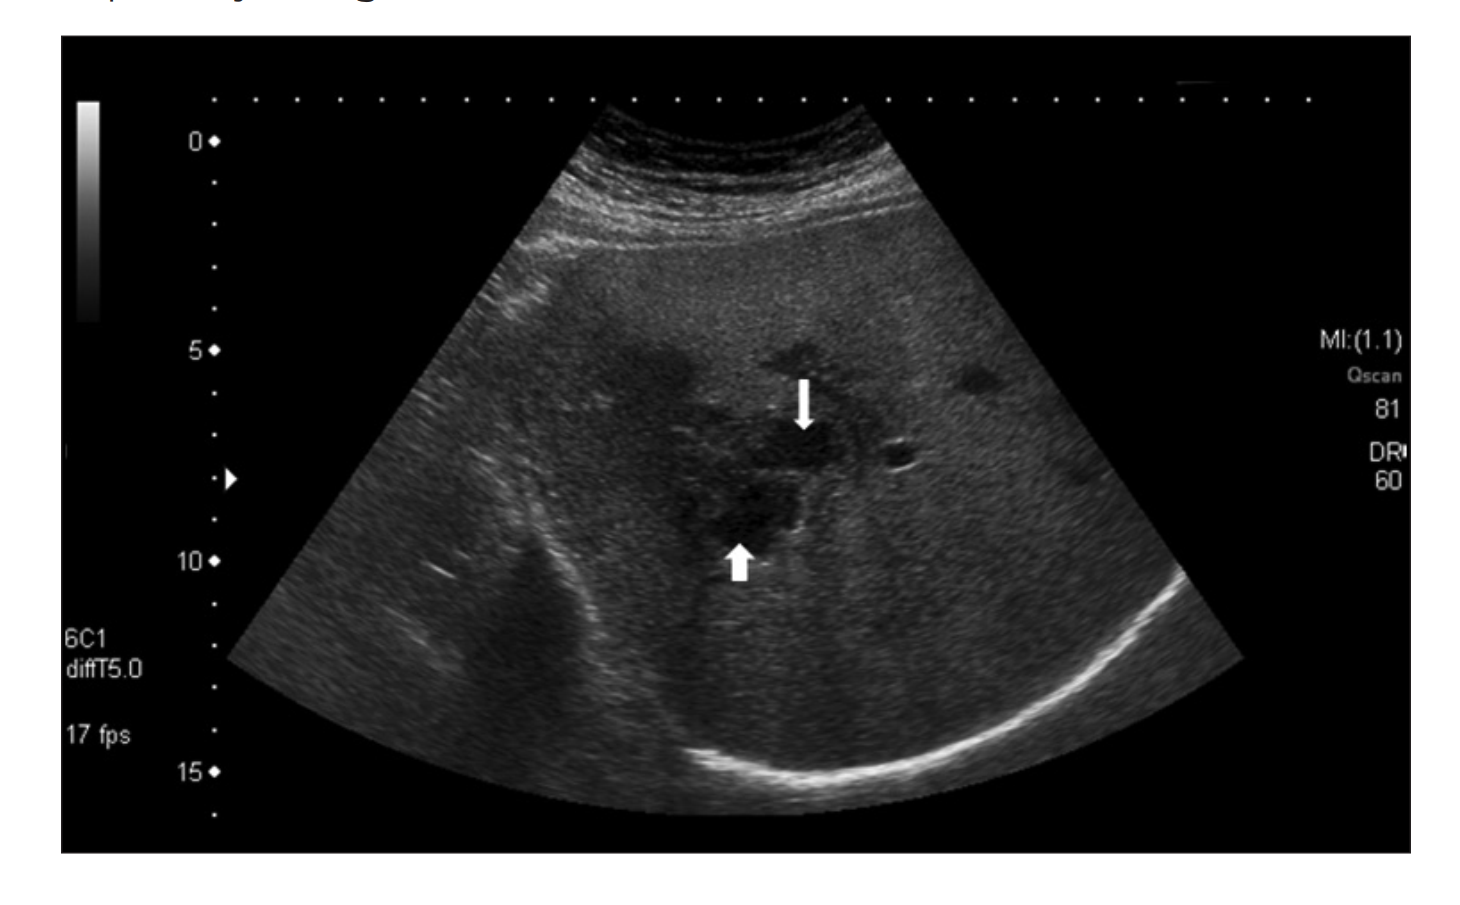

Xét nghiệm công thức máu ghi nhận, bệnh nhân có tình trạng tăng bạch cầu ái toan, xét nghiệm huyết thanh chẩn đoán Fasciola spp. dương tính. Kết quả siêu âm cho thấy có ổ áp xe ở gan, kích thước 5×8cm ở thai phụ 16 tuần và 7×8,4cm ở thai phụ 28 tuần.

Hình ảnh áp xe gan do sán lá gan lớn trên siêu âm. Ảnh: BVCC.